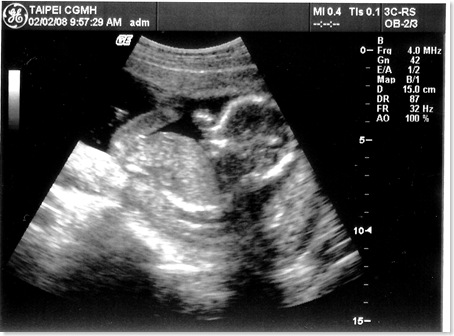

[產檢] 17週 寶寶頭大不是我的錯~~ ><

感覺有點擠~~

項  目 數 據 結 果 備 註

地點 02/02台北長庚 例行產檢

週數 17週

身長 15cm 體重約200g  ;  OK

心跳 150下/分鐘 OK

其他檢查 唐氏症抽血篩檢 預約高層次超音波

這星期主要還是看看超音波

量量寶寶的身長和估算體重有沒有在正常範圍

老婆邊照邊說寶寶頭很大..

沒想到醫生還跟著老婆瞎起鬨

說寶寶頭大像爸爸喔!!!   (明明寶寶頭的比例本來就比身體大得多...)   生氣...

這次照的超音波照也很清楚喔!!  真讚!!

寶寶還擺出鹹蛋超人的手交叉的動作..  五根手指己經看得清清楚楚了